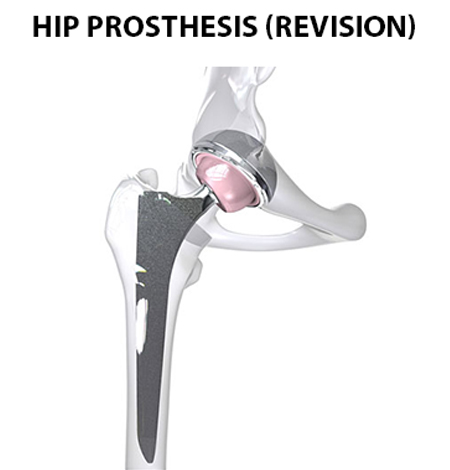

Revision Total Hip Replacement

A total hip replacement surgery goes through wear and tear with time, leading to a lot of pain and stiffness in the joint. It hinders easy movement and raises a need for a second surgery ??? Revision total hip replacement. The Total Hip Revision surgery involves removing and replacing a total or partial hip implant (prosthesis ??? body friendly implants) with a new one.

Revision Total Hip Replacement is recommended in case of infection or when the previous implant loosens, breaks or dislocates.

- Implant Loosening

- Breaks and infection

- Dislocations